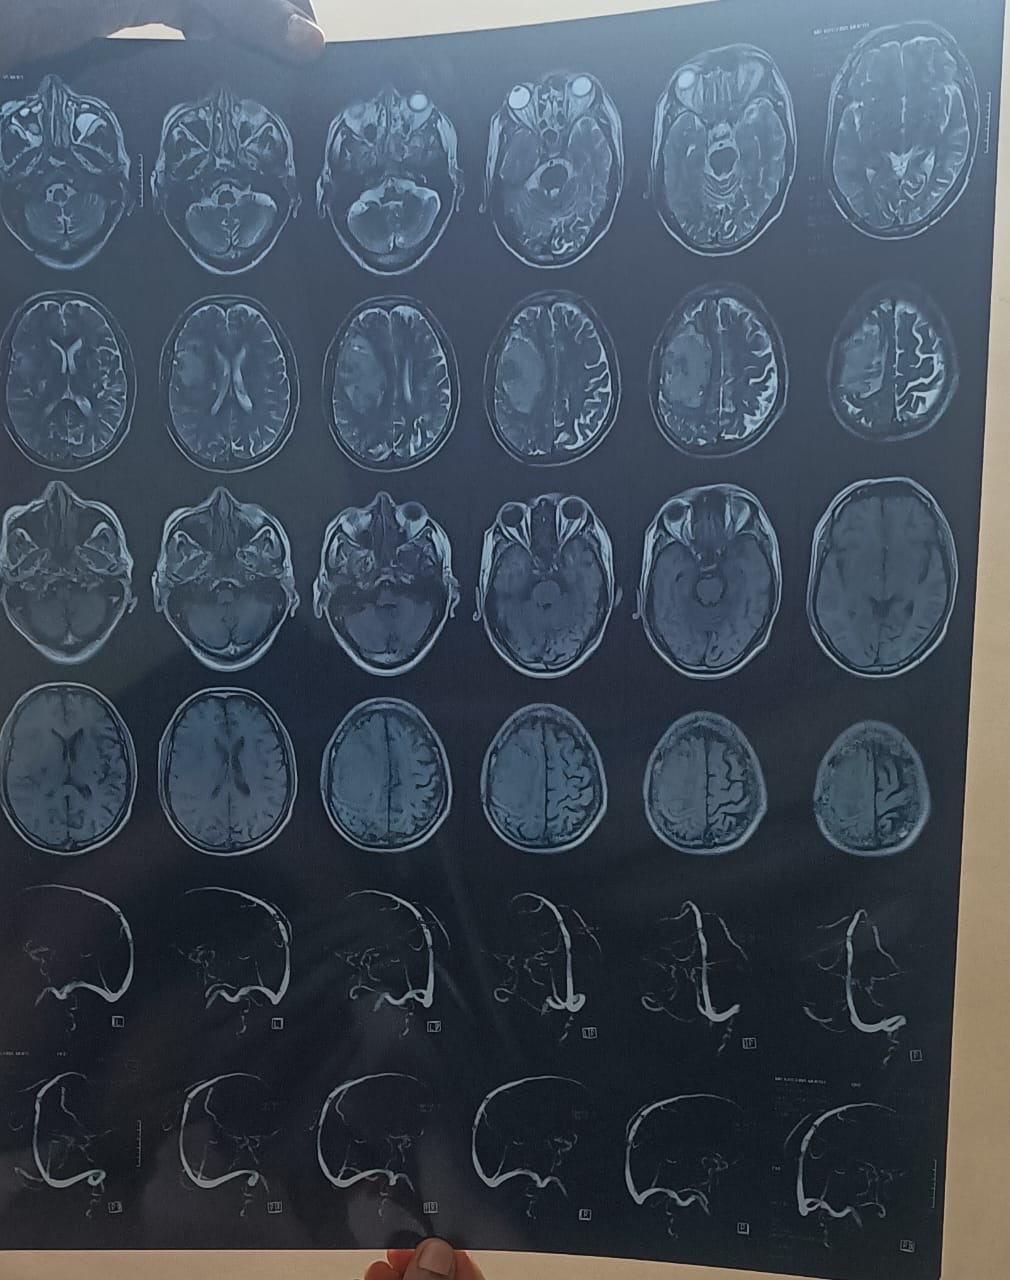

My name is Ajay Kumar Katkuri, resident of Fremont, CA. My father (age 60+) recently suffered a severe brain hemorrhage on the right side of his brain. The bleeding is large (over 5 cm), and it has extended into the brain’s ventricles, causing dangerous pressure and swelling. Doctors have confirmed a midline brain shift, which means urgent treatment is needed to prevent life-threatening complications or permanent disability.

Though he is conscious and recognizes us — which gives us hope — the condition is very serious and requires ICU care, potential surgery, and long-term rehabilitation.